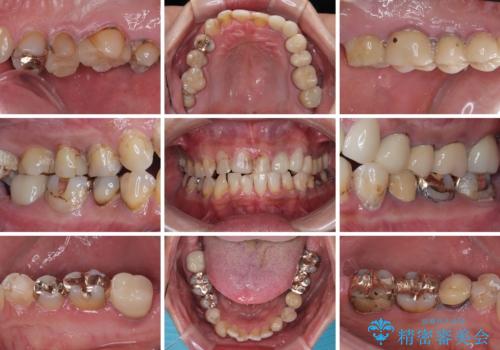

- すぐに欠けてしまう前歯や、むし歯で全顎的に処置された歯を気にして来院された患者様です。

元来むし歯が多く、さらに受け口傾向の咬み合わせを気にしていらっしゃいました。

当初はむし歯処置が必要な歯のみの治療予定でしたが、捻転や咬み合わせを可及的に改善したいとのことで、全顎的にオールセラミッククラウンにて補綴治療を行うこととしました。

反対咬合を補綴治療で改善すると、上唇へ歯が当たる感覚や、発音時の舌感覚が急激に大きく変化するため、違和感になれるまで時間を要することになります。